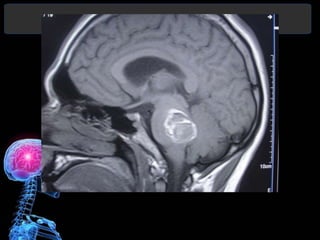

• TC permite mostrar la presencia de una

• Evidencia el tamaño, localización, edema

satelite, desplazamientos por efecto de

masa, invasión ventricular y la

hidrocefalia.

• Permite orientar el tratamiento y estimar

un pronóstico

DIAGNÓSTICO

• Algunos pacientes pueden presentar un

refuerzo periférico de la lesión al término

de la segunda semana, más frecuente en

hemorragias lobares y se puede confundir

con gliomas, metástasis o abscesos.

• RMN no ha significado una contribución

importante en el dx de ECV hemorrágico.